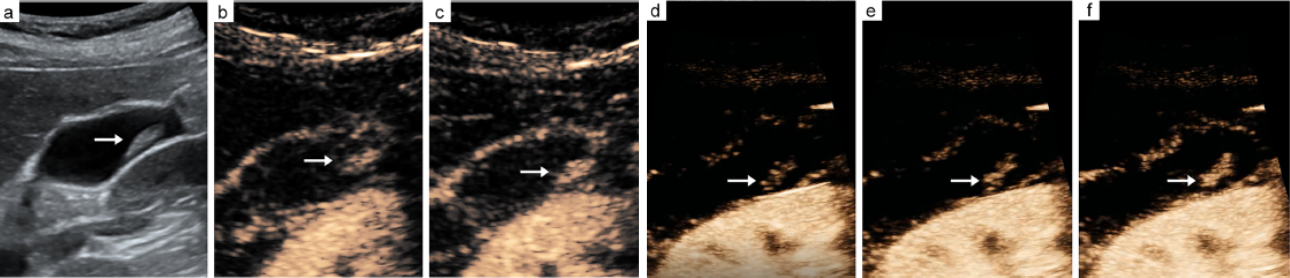

-- CEUS images of a cholesterol polyp lesion show dotted vascular type (b, c).

-- H-CEUS images of a cholesterol polyp lesion show dotted vascular type (d, e, f).

The arrow indicates the vascular type of a cholesterol polyp lesion